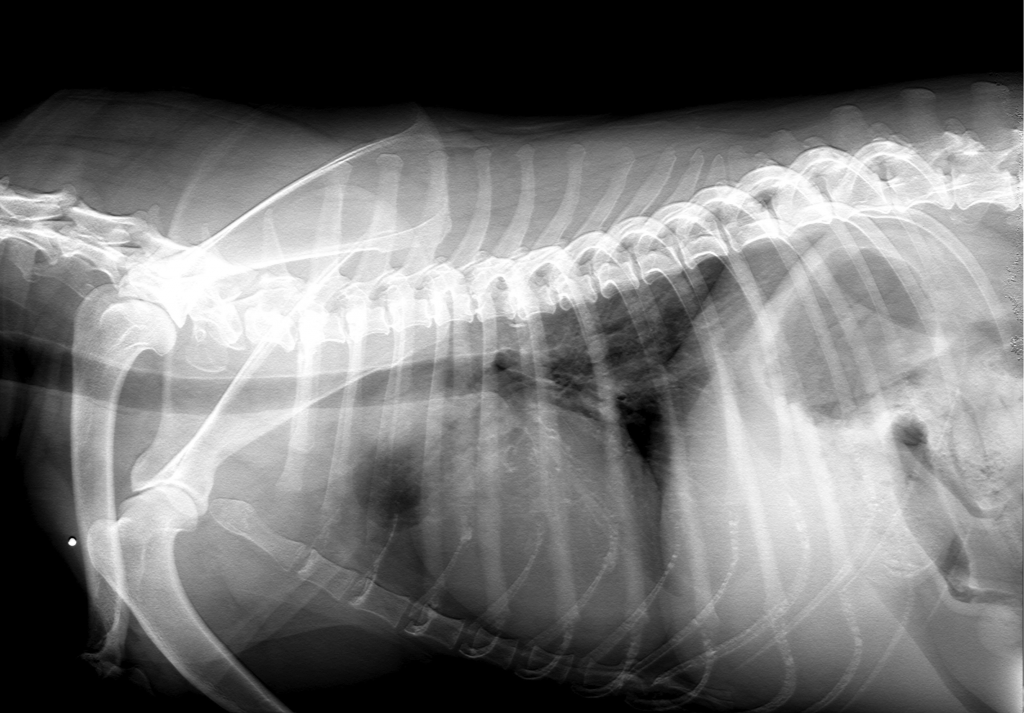

Radiographie abdominale:

Pour la recherche de pathologies concernant les organes abdominaux (foie, reins, rate, appareil digestif…)

Radiographie thoracique:

Visualisation de la trachée, des poumons, du coeur, etc…